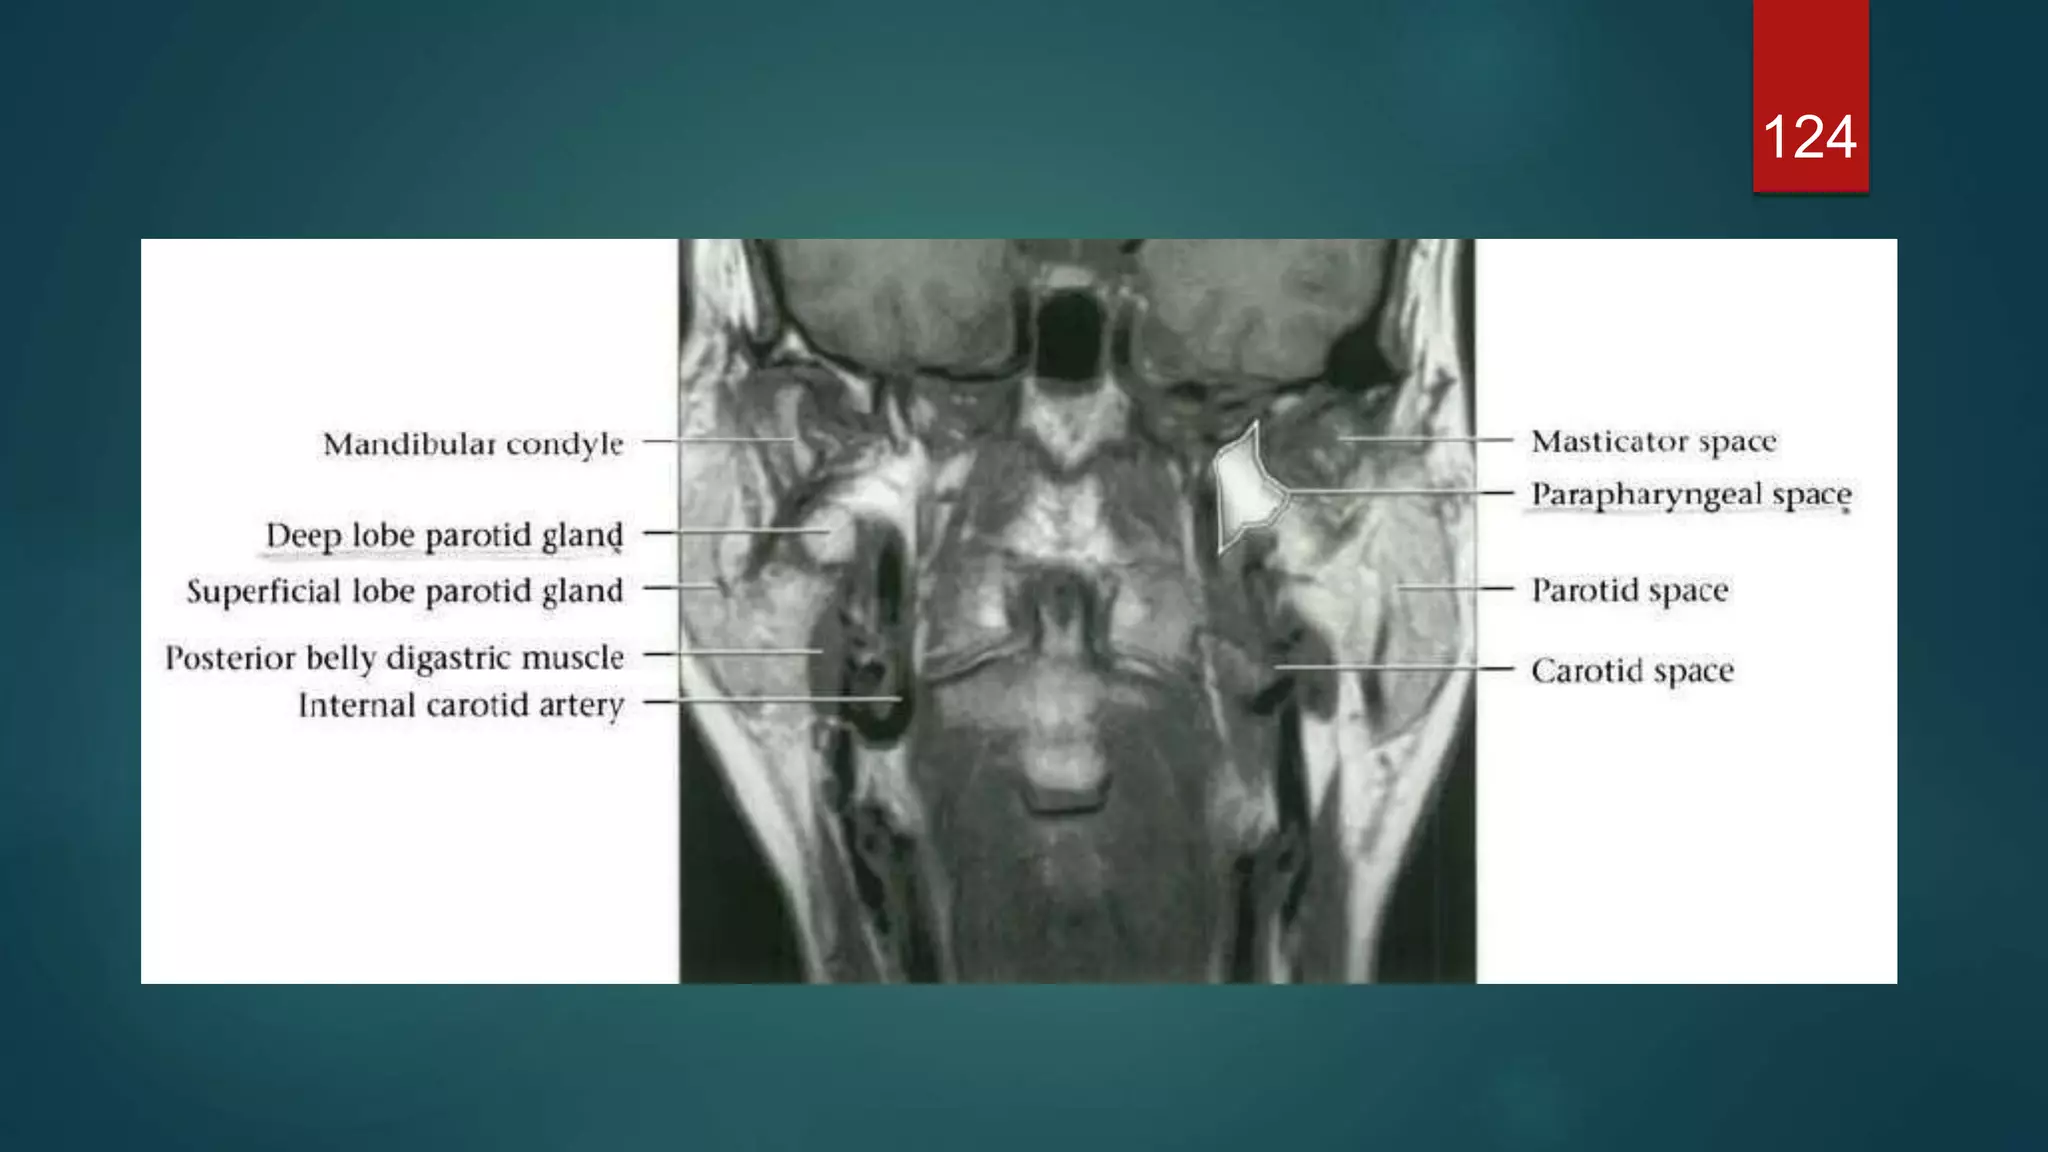

MRI

124